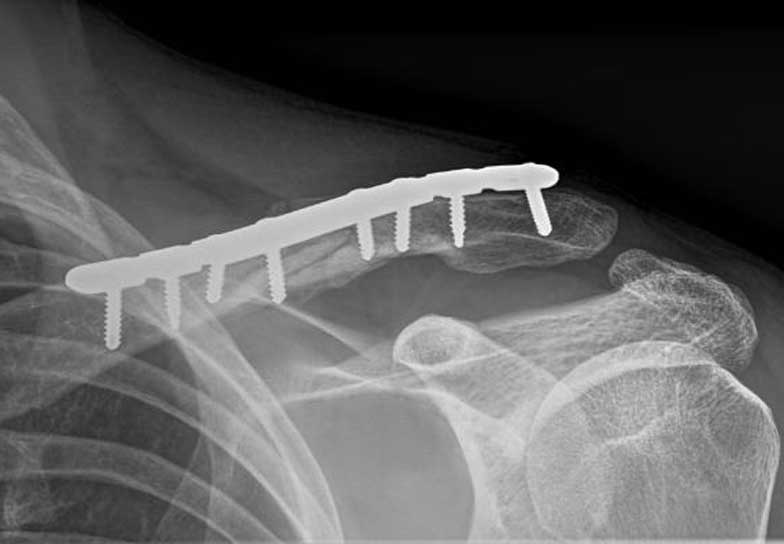

Generally all displaced fractures of the distal clavicle require surgery to increase the incidence of union. In my practice, the operation is performed by realigning the bones back to their original position using a plate and screws on top of the bone. The advantage of fixing them with a plate and screws generally means that you can start to move the arm a lot quicker and to also decrease the incidence of non-union.

How is the Operation Done?

The operation is performed with the patient under a general anaesthetic, in other words, completely asleep, and a small 3-4 cm incision is made under the collarbone, at the end of the shoulder. The fractured bone ends are exposed and put back into position using a plate and screws as shown below.

This fixation also needs reinforcement using special sutures around the plate and around the bone next to the clavicle called the coracoid process. The sutures are used to decrease the deforming forces from your shoulder muscles. In the majority of cases, in my hands, the operation is extremely successful resulting in the bone healing and the return of near normal function. In a small number of cases, the plate needs to be removed if it irritates the patient under the skin.